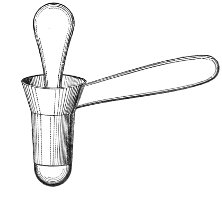

The Vaginal Speculum.—The speculum is an instrument through which a visual examination is made of the vagina, the external os uteri, and the vaginal cervix. A 29 great number of specula have been invented. At the present day the best two instruments of this class are the bivalve speculum, such as Goodell’s (Fig. 6), and the duck-bill speculum (Fig. 7), or perineal retractor, invented by Sims.

Fig. 7.—Sims’ speculum.

The Sims speculum enables us to make the most thorough inspection of the vagina, the vaginal vault, and the vaginal cervix. The Sims speculum is merely a hook or retractor for the perineum, and may be introduced with the woman in the dorsal position, the Sims position, or the genu-pectoral position. If the Sims speculum is introduced in the dorso-sacral position, it is necessary to hold forward the anterior vaginal wall in order to obtain a view of the cervix.

Fig. 10.—The Sims position.

The Sims position, which is also called the latero-abdominal position, is shown in Fig. 10. The woman is placed on the bed or table upon her left side. The side of the face is upon the pillow; the left arm is behind the back, so that the left breast rests upon the table. The thighs are flexed upon the abdomen at an angle of about 90° to the trunk. The right thigh is more flexed than the left, so that the right knee may touch the table above the left knee. The legs are flexed on the thighs. In this position there is a tendency for the intestines, following the force of gravity, to fall from the pelvis, 32 and for the uterus and other pelvic viscera to be drawn up. When the perineum is retracted with the blade of the Sims speculum, air will enter the vagina and the vaginal slit will become distended (Fig. 11). To facilitate inspection of the cervix it is usually necessary also to push forward the anterior abdominal wall by some kind of depressor, such as the one shown in Fig. 8.

Fig. 11.—The cervix uteri exposed with the Sims speculum.

The Sims speculum, with the woman in the dorsal, the Sims, or the knee-chest position, is the most useful instrument by which to expose the cervix uteri for any of the minor operations of gynecology. The manipulations of the operator are not hampered by working between metal walls.